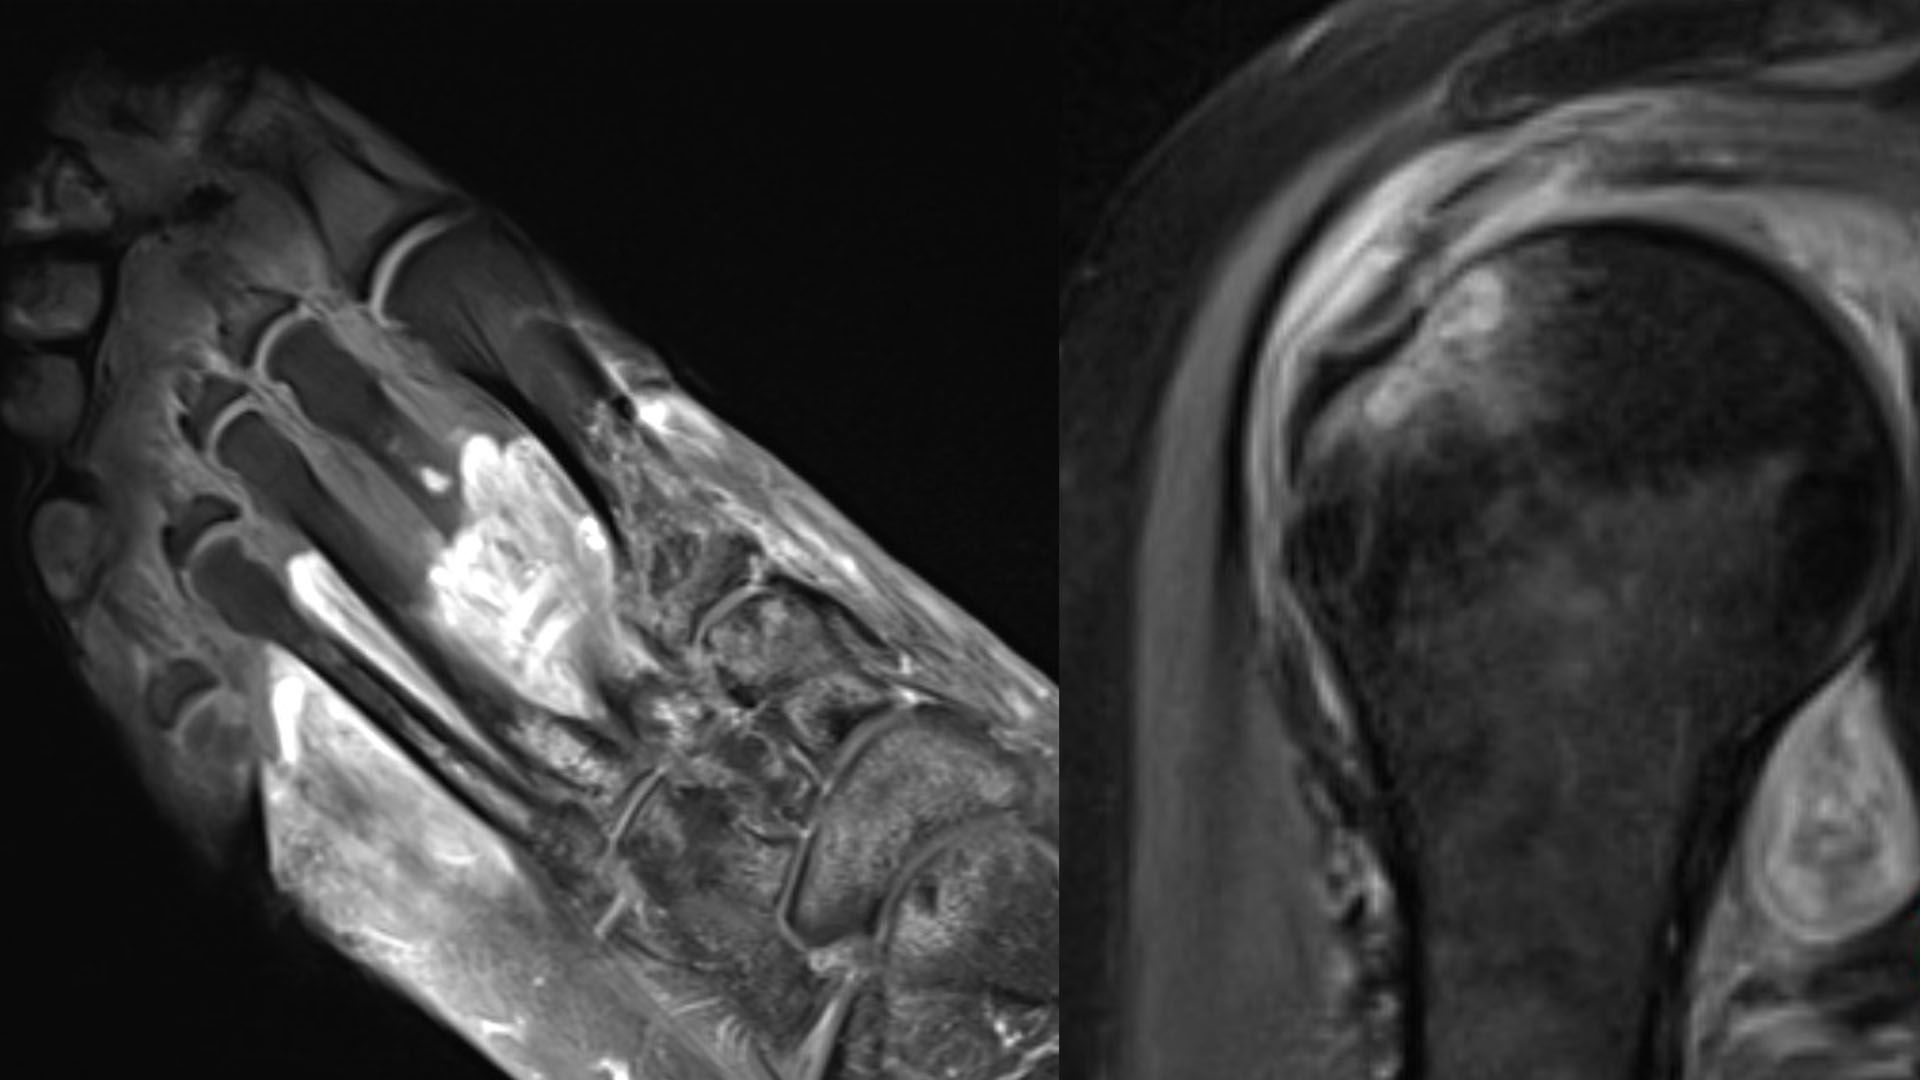

Imagen del estudio desarrollado por la Universidad de Northwestern sobre síntomas de la covid. Fuente: Universidad de Northwestern

"Podríamos ver edemas y cambios inflamatorios de los tejidos (líquido, hinchazón), hematomas (acumulaciones de sangre) o tejido desvitalizado (gangrena). En algunos pacientes, los nervios están lesionados (brillantes, agrandados) y en otros, el problema es un flujo sanguíneo deficiente (coágulos)", explica la doctora Swati Deshmuk para quien "es importante diferenciar entre lo que causa el virus directamente y lo que provoca que haga el cuerpo -resalta la doctora-. Es importante que los médicos sepan qué está sucediendo para poder tratar correctamente".

Por ejemplo, continúa, "si un paciente tiene dolor persistente en el hombro que comenzó después de contraer covid, su médico de atención primaria podría solicitar una resonancia magnética de ultrasonido".